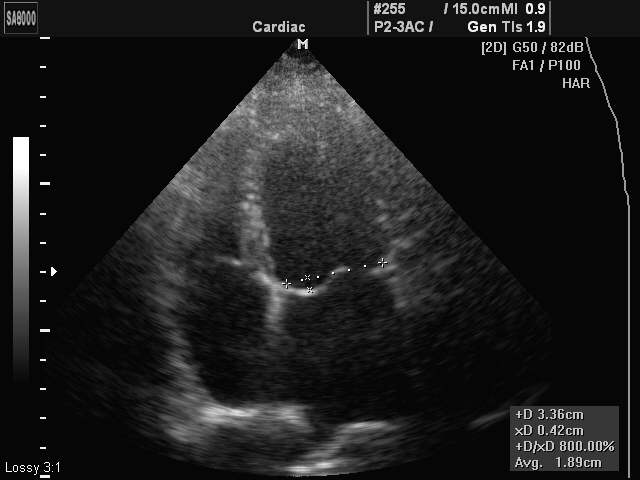

·Эхо-КГ - наиболее информативный метод при данной патологии. Он позволяет выявить провисание створок клапана, обнаружить гипертрофию левых отделов сердца, утолщение створок, удлинение сухожильных хорд, расширение митрального кольца, а также выявить косвенные признаки пролапса двустворчатого клапана (аневризму межпредсердной перегородки, расширение корня аорты);

Пролапс митрального клапана может быть первичным и вторичным (приобретенным), как было указано ранее. Также данное заболевание по УЗИ-признакам имеет три степени:

1 степень - провисание митрального клапана в полость левого предсердия менее 5 мм;

2 степень - пролабирование створок клапана до 10 мм;

3 степень - провисание двустворчатого клапана более 10 мм.